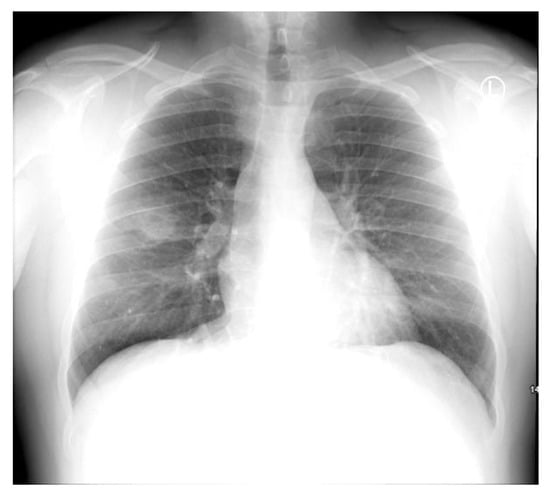

Noting that the patient had been discharged on amoxicillin/clavulanate, an antibiotic to which the isolated H. alvei was noted to be resistant, the patient was recalled for a follow-up review, repeat chest X-ray, and repeat blood tests 11 days after discharge. Remarkably, the repeat chest X-ray revealed significant interval improvement in the cavitating consolidation compared to the index X-ray performed 19 days previously (Figure 3), and repeat blood tests showed resolution of his previously raised inflammatory markers with a leukocyte count of 5.5 × 109/L, and CRP of 3 mg/dL. The patient also reported being symptom free. Following the reassuring review, he was discharged, with a further follow-up chest X-ray organized in six to eight weeks’ time, in accordance with international guidelines. This was performed ten weeks later, and reported almost complete resolution of the previously cavitating lesion in the RUL with only a very small residual lucency. A further follow-up X-ray will be performed in 6-8 weeks to ensure complete resolution.

Figure 3.

Follow-up chest X-ray on day 19 showing significant interval improvement in cavitating consolidation.